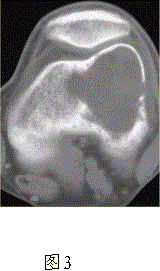

问题 患者女,35岁,左膝关节隐痛1年余,近1周加重,活动后明显疼痛。查体:左股骨下端外侧肿胀,压痛。行左膝关节正侧位CR,并行左膝关节CT扫描,见下图。 依据此病变的CT表现,以下说法正确的是

选项 A.病变边缘清晰 B.CT示左股骨外髁骨皮质不完整,提示病变为恶性或生长活跃 C.病灶内部密度不均 D.病灶周围可见软组织肿胀,提示为炎性病变 E.病灶无明显硬化缘 F.病灶呈中心性生长

答案 ABCE

解析 ABCE